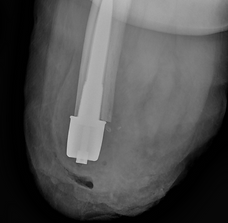

​Wankier Z, Taylor C, Drew A, Kubiak E, Agarwal J, Sinclair S. Use of computer tomography imaging for analyzing bone remodeling around a percutaneous osseointegrated implant. J Orthop Res. 2022 Sep;40(9):2065-2075. doi: 10.1002/jor.25247. Epub 2021 Dec 27. PMID: 34910325.​

Jeyapalina S, Beck JP, Bachus KN, Chalayon O, Bloebaum RD. Radiographic evaluation of bone adaptation adjacent to percutaneous osseointegrated prostheses in a sheep model. Clin Orthop Relat Res. 2014 Oct;472(10):2966-77. doi: 10.1007/s11999-014-3523-z. PMID: 24557934; PMCID: PMC4160482. ​

Jeyapalina S, Beck JP, Bloebaum RD, Bachus KN. Progression of bone ingrowth and attachment strength for stability of percutaneous osseointegrated prostheses. Clin Orthop Relat Res. 2014 Oct;472(10):2957-65. doi: 10.1007/s11999-013-3381-0. PMID: 24258685; PMCID: PMC4160472. ​